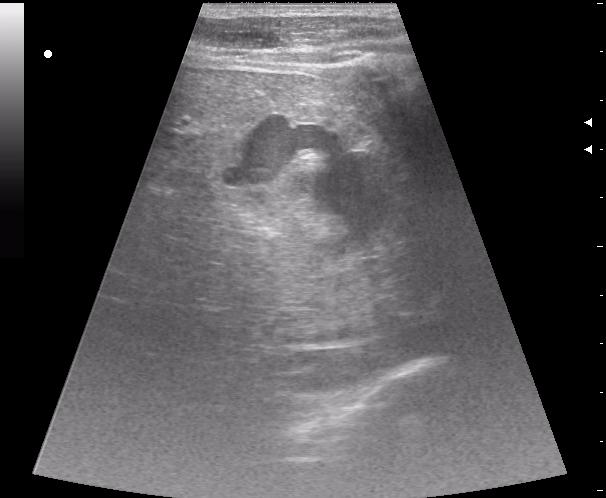

конец рабочего дня тоже "порадовал". Травма об руль велосипеда.

30 мин. после травмы